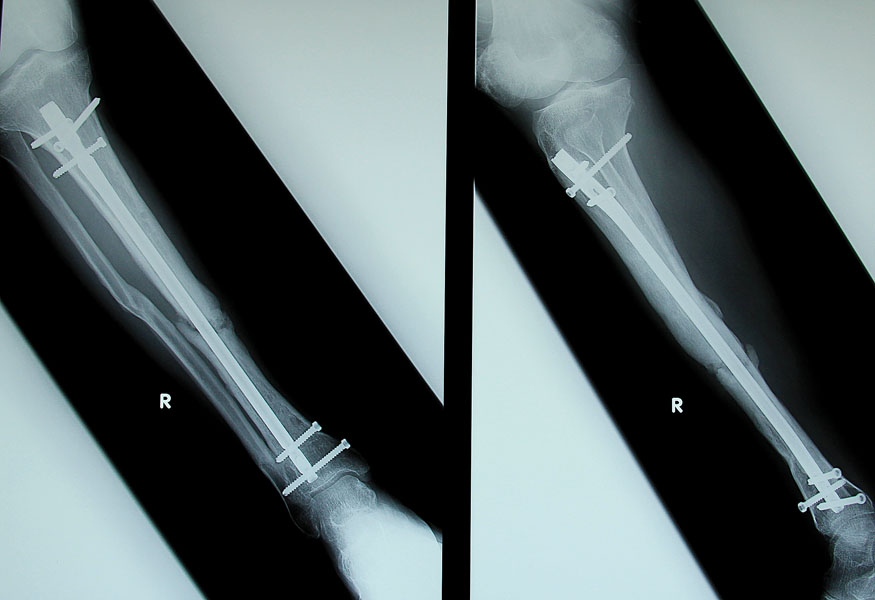

Obrażenia kciuka zwykle pojawiają się w wyniku kolizji z ogrodzeniem, oblodzoną nawierzchnią, a nawet z kijkami narciarskimi itp. Większość z tych urazów można wyleczyć w krótkim czasie, choć wszytko zależy od stopnia skomplikowania uszkodzenia. Złamania z przemieszczeniem, wieloodłamowe, otwarte, wewnątrzstawowe, a także uszkodzenia więzadeł pobocznych kciuka będą wymagały interwencji chirurgicznej i starannej opieki ortopedycznej.

Urazów nadgarstka najczęściej doznają snowboardziści. Prawdopodobieństwo uszkodzenia tej części ręki jest dwukrotnie wyższe w porównaniu z narciarzami. Do ciężkich złamań nadgarstka należą te, w których kości zostały wypchnięte ze swojego miejsca, kości przebiły skórę – elementy składowe nadgarstka zostały podzielone na wiele fragmentów.